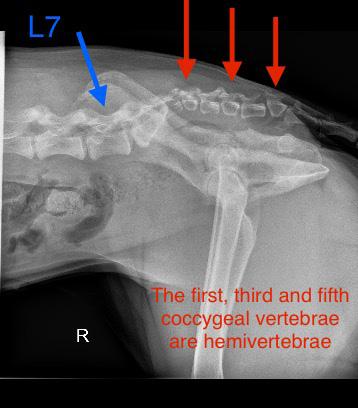

Ibought my first Rhodesian Ridgeback with my first paycheck out of Veterinary School in 1995 and have been in love with our smart and often naughty dogs ever since. Just before Christmas 2022, I lost my French imported Ridgie, “Grace” at 5 years and 1 week old to malignant visceral Mast Cell Tumor. She was my soul in a dog’s body, and as I watched our Great Dane “George” grieve for weeks, I decided to get another Ridgeback puppy. In February 2023, I went to a breeder and picked up little “Ruby”. She was a spunky little girl who could clearly keep up to her brothers. The puppies were crawling under a patio and exploring a big yard, so the small bump at the base of her back I thought was an injury. She was running around and seemed fine otherwise. I had a dog-trainer friend go with me, and so we flew home to Arizona with little “Ruby” between us on the plane. The breeder suggested that I could show her as she had great blood lines.

by Animal Biome (animalbiome.com) to help her alleviate the loose stools. We improved her diet, and added fish oils and other supplements. She strained to have a bowel movement from the time she got to our house as an 8 week old puppy, and has done so ever since. At first, she would walk around 10 m to complete her bowel movement. She almost “overflow defacated”. At about 10 weeks old she cried out as I was sitting on the floor playing with her and my hand bumped into her lower back. I took her to my hospital and x-rays of her back were done. She looked like a French Bulldog beyond her sacrum and into her tail. She had a pronounced wedge shaped coccygeal vertebrae (called hemivertebrae) in the location of her bump.

dog, and it appears she is not. Her latest X-rays show the first, third and fifth coccygeal vertebrae are actually hemivertebrae creating a really uneven tailset area. An MRI might be in her future to help identify the reason for the pain and prolonged defecation, but not yet. She is a ‘high tail kink’ dog at this time. Kinked tails are supposed to be innocuous. But, that is not the case here. Her pain is real. My family and I will care for her and offer her a performance life as part of our pack. We lovingly call her “Aunt Ruby” already. She has had chiropractic work done and has had sporadic doses of anti-inflammatory medication if she is hurting.

Ruby in Stack Kink in tailset and her xrays